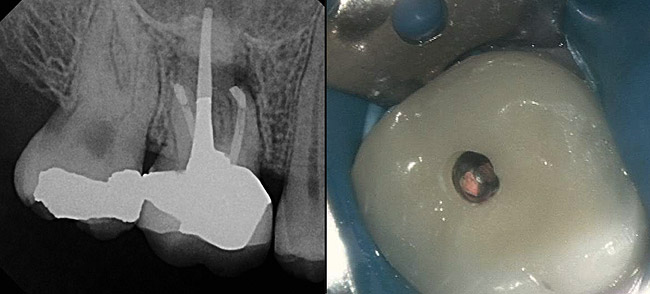

A 42-year-old woman presents for emergency treatment with a chief complaint of severe pain over the past 2 days in her upper jaw. The patient attributes the pain to tooth No. 3, as it received endodontic therapy 2 years ago (Figure 1). She complains of severe (pain score of 9/10), dull, throbbing pain in the right side of the face, jaws, and cheek that radiates into the temple with episodes of acute sharp pain, which is more severe at night, and appears to be stemming from the maxillary right molar (tooth No. 3). The patient has been awakened with pain over the past couple of nights and takes 600 mg of ibuprofen for relief. The patient also complains of a history of cold sensitivity from that tooth over the past couple of months and a history of low-grade chewing pain ever since the root canal. The past dental history is significant for a recent prophylaxis and fluoride treatment within the past month, and two fillings in the maxillary left side (teeth Nos. 12 and 14), and a crown in tooth No. 30 within the past 3 months (Figure 2). The patient’s medical history is insignificant, with no allergies reported. Extraoral tests are insignificant for objective findings. Intraoral tests show that tooth No. 3 is sensitive to percussion (3/10) and the radiograph shows a localized periapical radiolucency associated with the mesiobuccal (MB) root of this tooth.

At this point, a diagnosis of previous endodontic therapy with a failing MB root in tooth No. 3 appears clear. But whether the cause of the patient’s chief complaint is this pathology or not requires further investigation. Because the patient complains of severe pain and increasing thermal sensitivity over the past few weeks, testing should be directed toward a diagnosis of a degenerating vital pulp and not a tooth with a history of endodontic treatment. Necrotic teeth or failing endodontically treated teeth do not manifest thermal sensitivity. This is why clinical tests, in combination with an emphasis on duplicating the patient’s chief complaint, are necessary to arrive at the correct diagnosis. After clinical tests are performed, tooth No. 30 is found to a have a severe, lingering response to the cold test and is slightly “different” to percussion. This test duplicates the patient’s chief complaint. Endodontic therapy in this tooth is performed and pain is relieved (Figure 3). Tooth No. 3, with its apical pathology around the MB root, is later retreated to address a missed second mesiobuccal canal (MB2), relieving the patient from the chewing pain (Figure 4).

Figure 2  Preoperative view of tooth No. 30.

Figure 2

Figure 3  Postoperative view of tooth No. 30.

Figure 3